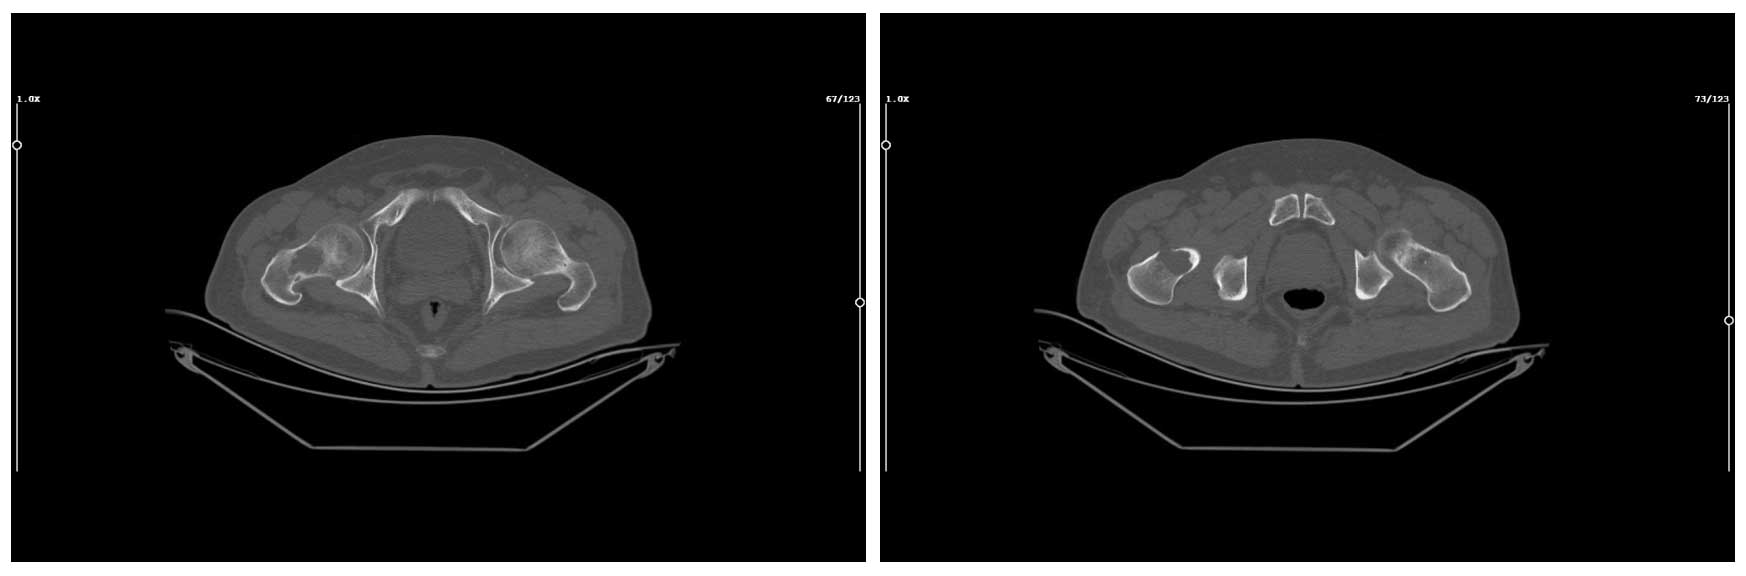

Ameliyat Öncesi: Tomografide ek olarak anterior kortekste destrüksiyon görünmekte.